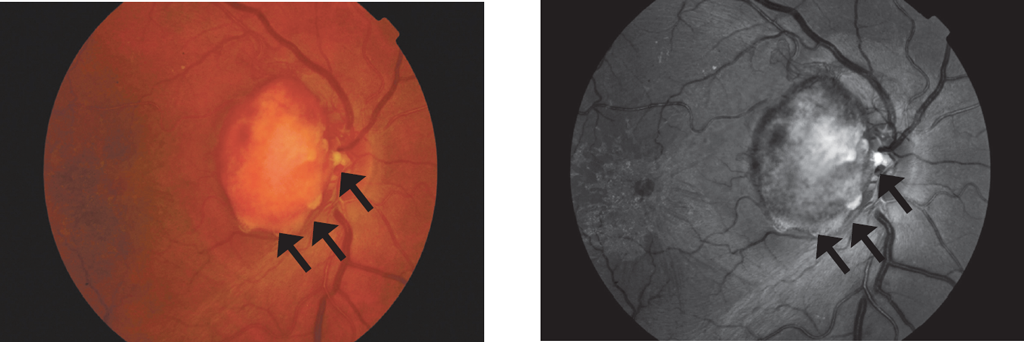

Figure 5 shows a typical astrocytoma of the optic nerve head, and Figure 6 shows amelanotic melanoma of the juxtapapillary localization. The most characteristic symptoms of astrocytoma are clear contours; yellow, orange, and pink color or a combination thereof; and multilobar structure (often having a mulberry shape). Retinal and optic head astrocytomas are most often observed in tuberous sclerosis complex but can also develop with type 1 neurofibromatosis or without any underlying medical condition [1, 2, 9, 14]. Typical astrocytoma of the optic nerve head often has a mulberry shape due to multiple calcification nodules. However, the fact that astrocytomas may not be accompanied by calcification sites [1, 2] should be remembered. Both tumors may be accompanied by secondary retinal detachment [2, 9]. Amelanotic melanoma with juxtapapillary localization can spread to the optic nerve head but does not directly originate from it, as in the clinical case presented. In addition to the typical lenticular form, melanoma can be fungiform (or take the form of a cufflink) due to the penetration of the Bruch’s membrane and infringement of the neoplasm apex in the defect [1]. Choroidal melanoma can often have two humps, indicating the presence of two growth epicenters, usually while developing from the previous nevus. However, we have never observed a multilobate structure of the choroidal melanoma. At the B-scan ultrasound imaging for vascular membrane melanoma, echogenicity is sub-average, sometimes with acoustic cavities and choroidal excavation [1, 2]. Melanoma can penetrate into the optic nerve head with circular growth, but the tumor prominence above it is not the highest.

Fig. 5. Astrocytoma of the optic nerve head in 56 year old man. Nodules of calcification are marked with black arrows, better visualization in red-free light

Рис. 5. Астроцитома головки зрительного нерва у мужчины 56 лет. Узлы кальцификации показаны чёрными стрелками, они лучше визуализируются в бескрасном свете